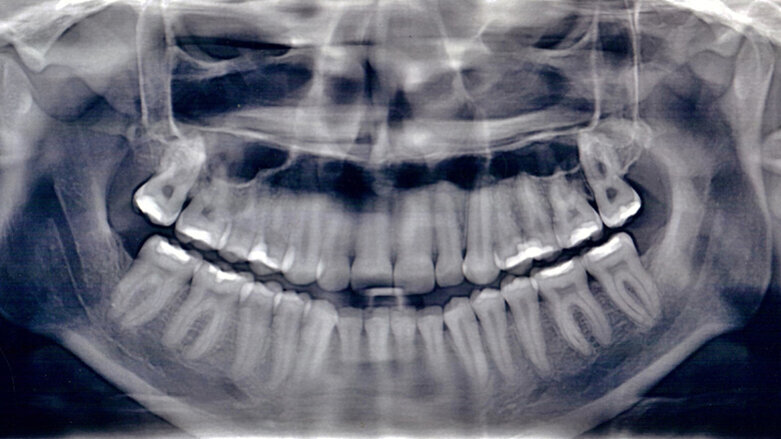

OPG snímek z průběhu léčby (Fotografie: Dr. Gary Brigham)